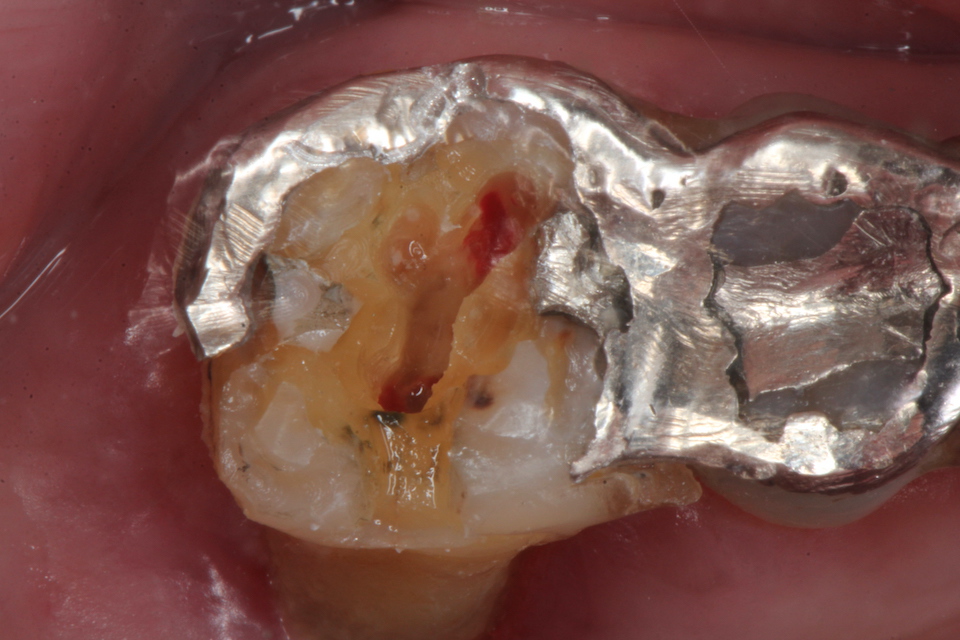

60代女性、左上6、咬合性外傷性による歯髄炎、自発痛++、歯ぎしり、動揺度2.5

ということで、歯髄は死にかけているな。。と思って天蓋を除去してみた。

天蓋を穿通した。少し出血している。死にかかっている歯に麻酔は要らない。麻酔とは健全な痛みを感じる歯を削る時に必要なだけだ。麻酔が必要な歯を削るということは僕に言わせれば、過剰診療と言っても良い。

上顎6の根管は3つあるはずだ。探している

口蓋根の出血は少ない。ほとんど失活している